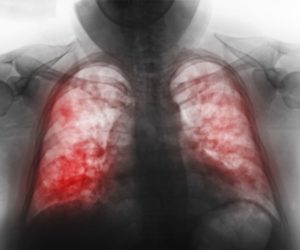

- Рентгенография. Это обязательное условие, которое требуется выполнить пациенту. С помощью рентгеновского снимка врач сможет точно увидеть состояние легких, есть ли затемнения или другие очаги воспаления в органе.